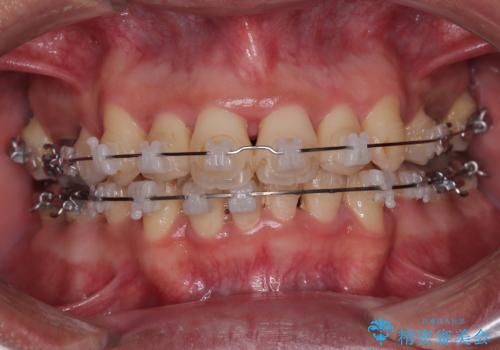

捻れて前に出ている前歯 ワイヤー装置での非抜歯矯正